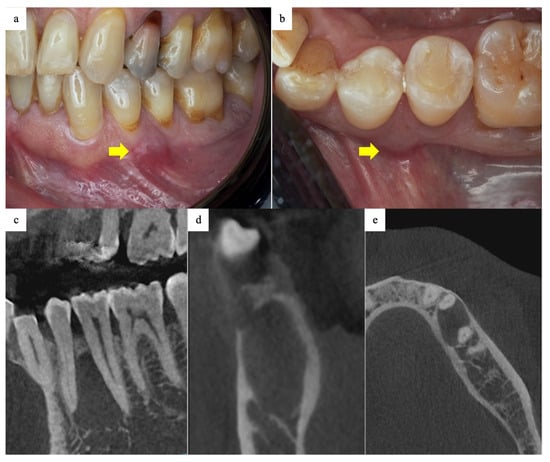

2.1. History and Examination

2.2. Surgical Phase